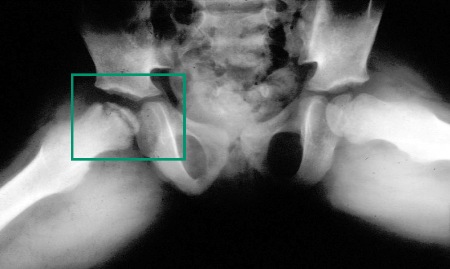

- radiografia do quadril (incluindo incidência em posição de rã):

achatamento, esclerose e, por fim, fragmentação e colapso da epífise femoral, com alargamento do colo do fêmur

- ressonância nuclear magnética (RNM) do quadril:

vascularidade reduzida da cabeça do fêmur pode ser observada no início da doença; achatamento, esclerose e, por fim, fragmentação e colapso da epífise femoral, com alargamento do colo do fêmur